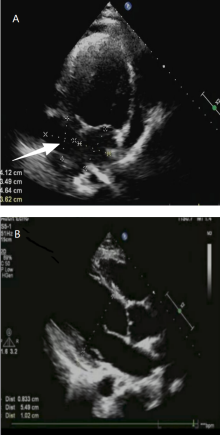

This article reports the diagnosis and treatment process of one case of sparganosis mansoni. The patient was a young man, admitted to the hospital due to “substernal pain accompanied by shortness of breath for over a week”. Cardiac MR and enhanced chest CT examinations revealed large amount of pericardial effusion. Hemorrhagic exudate was found by pericardiocentesis, and routine laboratory examination of the pericardial effusion showed a significant increase in the proportion of lymphocytes and adenosine deaminase (ADA) levels. He was initially suspected to be tuberculosis infection, yet no evidence could support this conclusion by additional laboratory studies, including mNGS of the pericardial effusion, T-SPOT.TB, and sputum AFB smear. Further inquiry into the medical history revealed that the patient had a history of consuming raw frog meat. Both routine blood test and biochemical analysis of the pericardial effusion indicated elevated eosinophils, and the serum antibody test positive for Spirometra mansoni. Consequently, empirical therapy with praziquantel was initiated. After medication, the patient’s clinical symptoms were significantly improved, and follow-up examination showed resolution of the pericardial effusion. The patient was ultimately diagnosed with an infection caused by sparganosis mansoni.